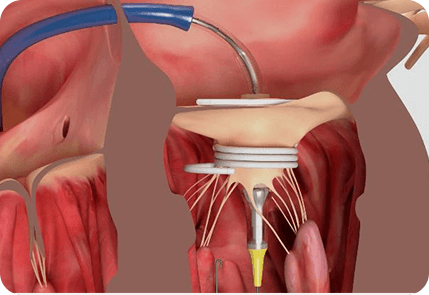

5.CT应用于二尖瓣三尖瓣的治疗

同样,心脏CT已成为较新的瓣膜置换术前不可或缺的工具,特别是对于经导管二尖瓣和三尖瓣介入治疗(Ref 42)。

例如,

经导管二尖瓣置入术存在植入后左室流出道(LVOT)阻塞和随后的心力衰竭的风险,并且是大约7%-9%的手术中可能发生的令人担忧的并发症。

当植入的装置将二尖瓣前叶移位到左心室流出道,从而使左室流出道变窄,导致所谓的新的左室流出道时,就会发生这种并发症。

如下图所示,心脏CT图像可以在术前心脏CT扫描上生成模拟的新左室流出道(Ref 43)。

新的左心室流出道已被迅速采用为预测植入后左室流出道压差风险的关键解剖学指标,并用于瓣膜植入前的筛查。

在经导管三尖瓣植入术的术前和术后评估上,CT也发挥了非常重要的作用。

下图为经导管三尖瓣植入术(EVOQUE,Edwards Lifesciences)的术前和术后CT扫描图像(Ref 44):

A:Evoque心脏瓣膜,包含一个自膨胀的镍钛合金框架,带有牛心包叶、环内密封裙和心室锚。

B:28-F Evoque三尖瓣系统

C:收缩期的横断面测量

D:舒张期的横断面测量